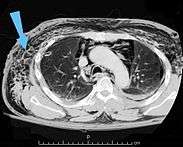

Significant cases of subcutaneous emphysema are easy to diagnose because of the characteristic signs of the condition.[1] In some cases, the signs are subtle, making diagnosis more difficult.[13] Medical imaging is used to diagnose the condition or confirm a diagnosis made using clinical signs. On a chest radiograph, subcutaneous emphysema may be seen as radiolucent striations in the pattern expected from the pectoralis major muscle group. Air in the subcutaneous tissues may interfere with radiography of the chest, potentially obscuring serious conditions such as pneumothorax.[19] It can also and reduce the effectiveness of chest ultrasound.[28] On the other hand, since subcutaneous emphysema may become apparent in chest X-rays before a pneumothorax does, its presence may be used to infer that of the latter injury.[13] Subcutaneous emphysema can also be seen in CT scans, with the air pockets appearing as dark areas. CT scanning is so sensitive that it commonly makes it possible to find the exact spot from which air is entering the soft tissues.[13] In 1994, M.T. Macklin and C.C. Macklin published further insights into the pathophysiology of spontaneous Macklin's Syndrome occurring from a severe asthmatic attack.